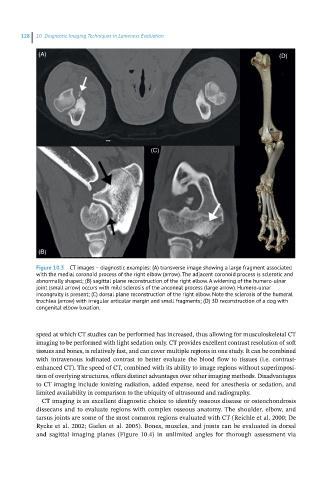

Figure 10.3 CT images – diagnostic examples: (A) transverse image showing a large fragment associated

with the medial coronoid process of the right elbow (arrow). The adjacent coronoid process is sclerotic and

abnormally shaped; (B) sagittal plane reconstruction of the right elbow. A widening of the humero‐ulnar

joint (small arrow) occurs with mild sclerosis of the anconeal process (large arrow). Humero‐ulnar

incongruity is present; (C) dorsal plane reconstruction of the right elbow. Note the sclerosis of the humeral

trochlea (arrow) with irregular articular margin and small fragments; (D) 3D reconstruction of a dog with

congenital elbow luxation.